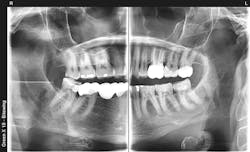

Occlusion is a forgotten area of dentistry, but it is more important now than ever before. A significant number of adult patients have grinding issues or clenching bruxism. With the advent of zirconia into dentistry, numerous good and bad situations have occurred. Zirconia is a substitute for steel. It’s strong, wear resistant, and serves patients very well, but the downside is clear. When two pieces of zirconia are in malocclusion, the damage to natural tooth abutments or implants is a well-known problem. Improper occlusion of zirconia restorations is one of the major reasons for implant failure, temporomandibular disorders, and broken teeth. Becoming more educated about occlusion and sharing your knowledge with dental peers would be a great service.

Dental technologies such as cone beam radiology, scanners, 3D printing, new endodontic debridement methods, and laser resin curing are growing daily (figure 3). Every new technology you introduce into your practice requires education, experience, better patient care, and will foster excitement in your practice.